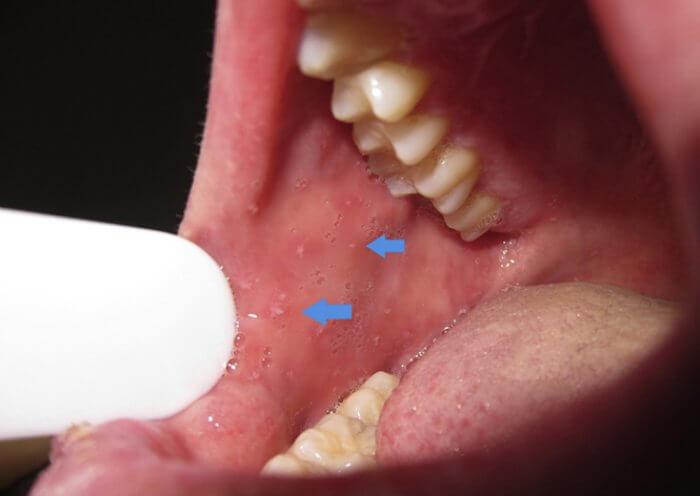

El sarampión es una infección grave que se caracteriza por fiebre alta, enantema, tos, coriza, conjuntivitis y un exantema prominente. Después de un período de incubación de 8-12 días, la fase prodrómica comienza con un cuadro de febrícula seguido por la aparición de conjuntivitis con fotofobia, coriza, tos intensa y aumento de la fiebre. El enantema es el signo patognomónico del sarampión y aparece 1-4 días antes del inicio del exantema Aparece en primer lugar como unas lesiones rojizas individuales con unos puntos blanco azulado en el centro, en la cara interna de las mejillas, a nivel de los premolares. Pueden extenderse y afectar a los labios, el paladar duro y las encías. También pueden aparecer en los pliegues conjuntivales y en la mucosa vaginal. Las manchas de Koplik se han descrito en el 50-70% de los casos de sarampión, pero es probable que aparezcan en la gran mayoría de ellos.